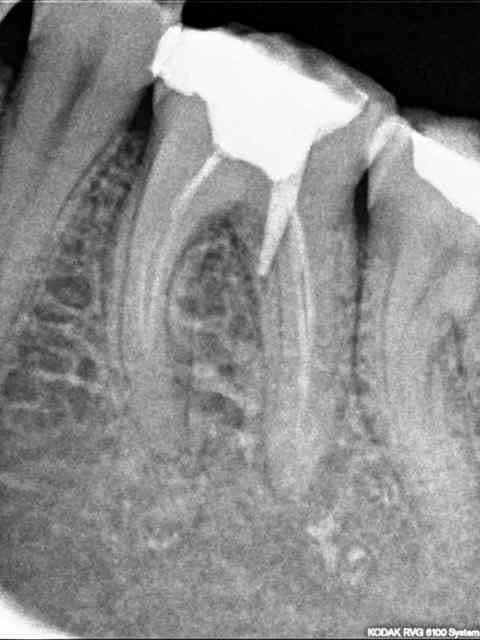

Vu en garde dimanche dernier :

Tenon "type SC33" posé au milieu d'un pâté de résine le lundi. Patiente a douleur très vive le mardi : praticien fait retouche occlusale "ça va passer". Le jeudi, rebelote "ça va passer".

Le dimanche, c'est toujours pas passé...

J'ai déposé le tenon, mis du CaOH et adressé à un confère orienté endo pour RTE + pose MTA.